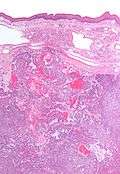

| Low magnification micrograph of a polymorphous low-grade adenocarcinoma, showing the typical variation of architectural arrangement. H&E stain. | |

PLGAs consist of a monomorphous cell population that has a varied histologic morphology.

Microscopically, its histology can be confused with an adenoid cystic carcinoma and a pleomorphic adenoma.